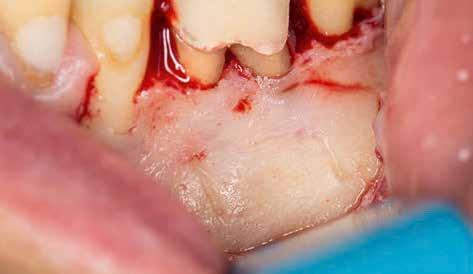

A preprotetikai fázisban el kell látnunk a diagnosztizálásra került kórfolyamatokat, megfelelő pozícióba kell állítanunk a megtartani kívánt fogakat, pótolnunk kell az elvesztett csontállományt, valamint gondoskodnunk kell az íny megfelelő állapotáról. Ha szükség van rá, úgy a foghiányok pótlására szolgáló dentális implantátumok is ebben a fázisban kerülnek behelyezésre. Általánosságban elmondható, hogy azokat a kezeléseket, amelyek befejezése biológiai okok miatt hosszú időt vesz igénybe (pl.: fogszabályozás, csontpótlás, implantáció), a lehető leghamarabb érdemes elkezdeni.

A fogszabályzó kezelések egyik legfontosabb célja, hogy elérjük a lehető legharmonikusabb interokkluzális fogérintkezéseket, továbbá az állcsont relációs helyzetének frontális és szaggitális síkban is megfelelőnek kell lennie. A fogszabályzás befejezésekor a fogpozícióknak nem orthodonciai, hanem protetikai szempontok szerint kell ideálisnak lenniük. Az Invisalign ClinCheck szoftver (Align Technology) segítségével a protetikus az orthodontussal együtt meg tudja határozni azokat a végső fogpozíciókat, amelyek a lehető legjobb végeredmény biztosításához elengedhetetlenek. Bizonyos klinikai paramétereket, mint a fogak klinikai koronájának nagyságát, az egyes fogak fogíven belüli optimális pozícióját, a fogívek egymáshoz viszonyított helyzetét, a fogak között látható rések nagyságát, a frontfogak tengelyének dőlését, az overjet és overbite mértékét már a kezelések megkezdése előtt pontosan definiálni kell. Ezeket az adatokat viszont csak a tervezett végleges fogpótlás ismeretében lehet meghatározni, ezért van szükség az orthodontus és a protetikus szoros együttműködésére.